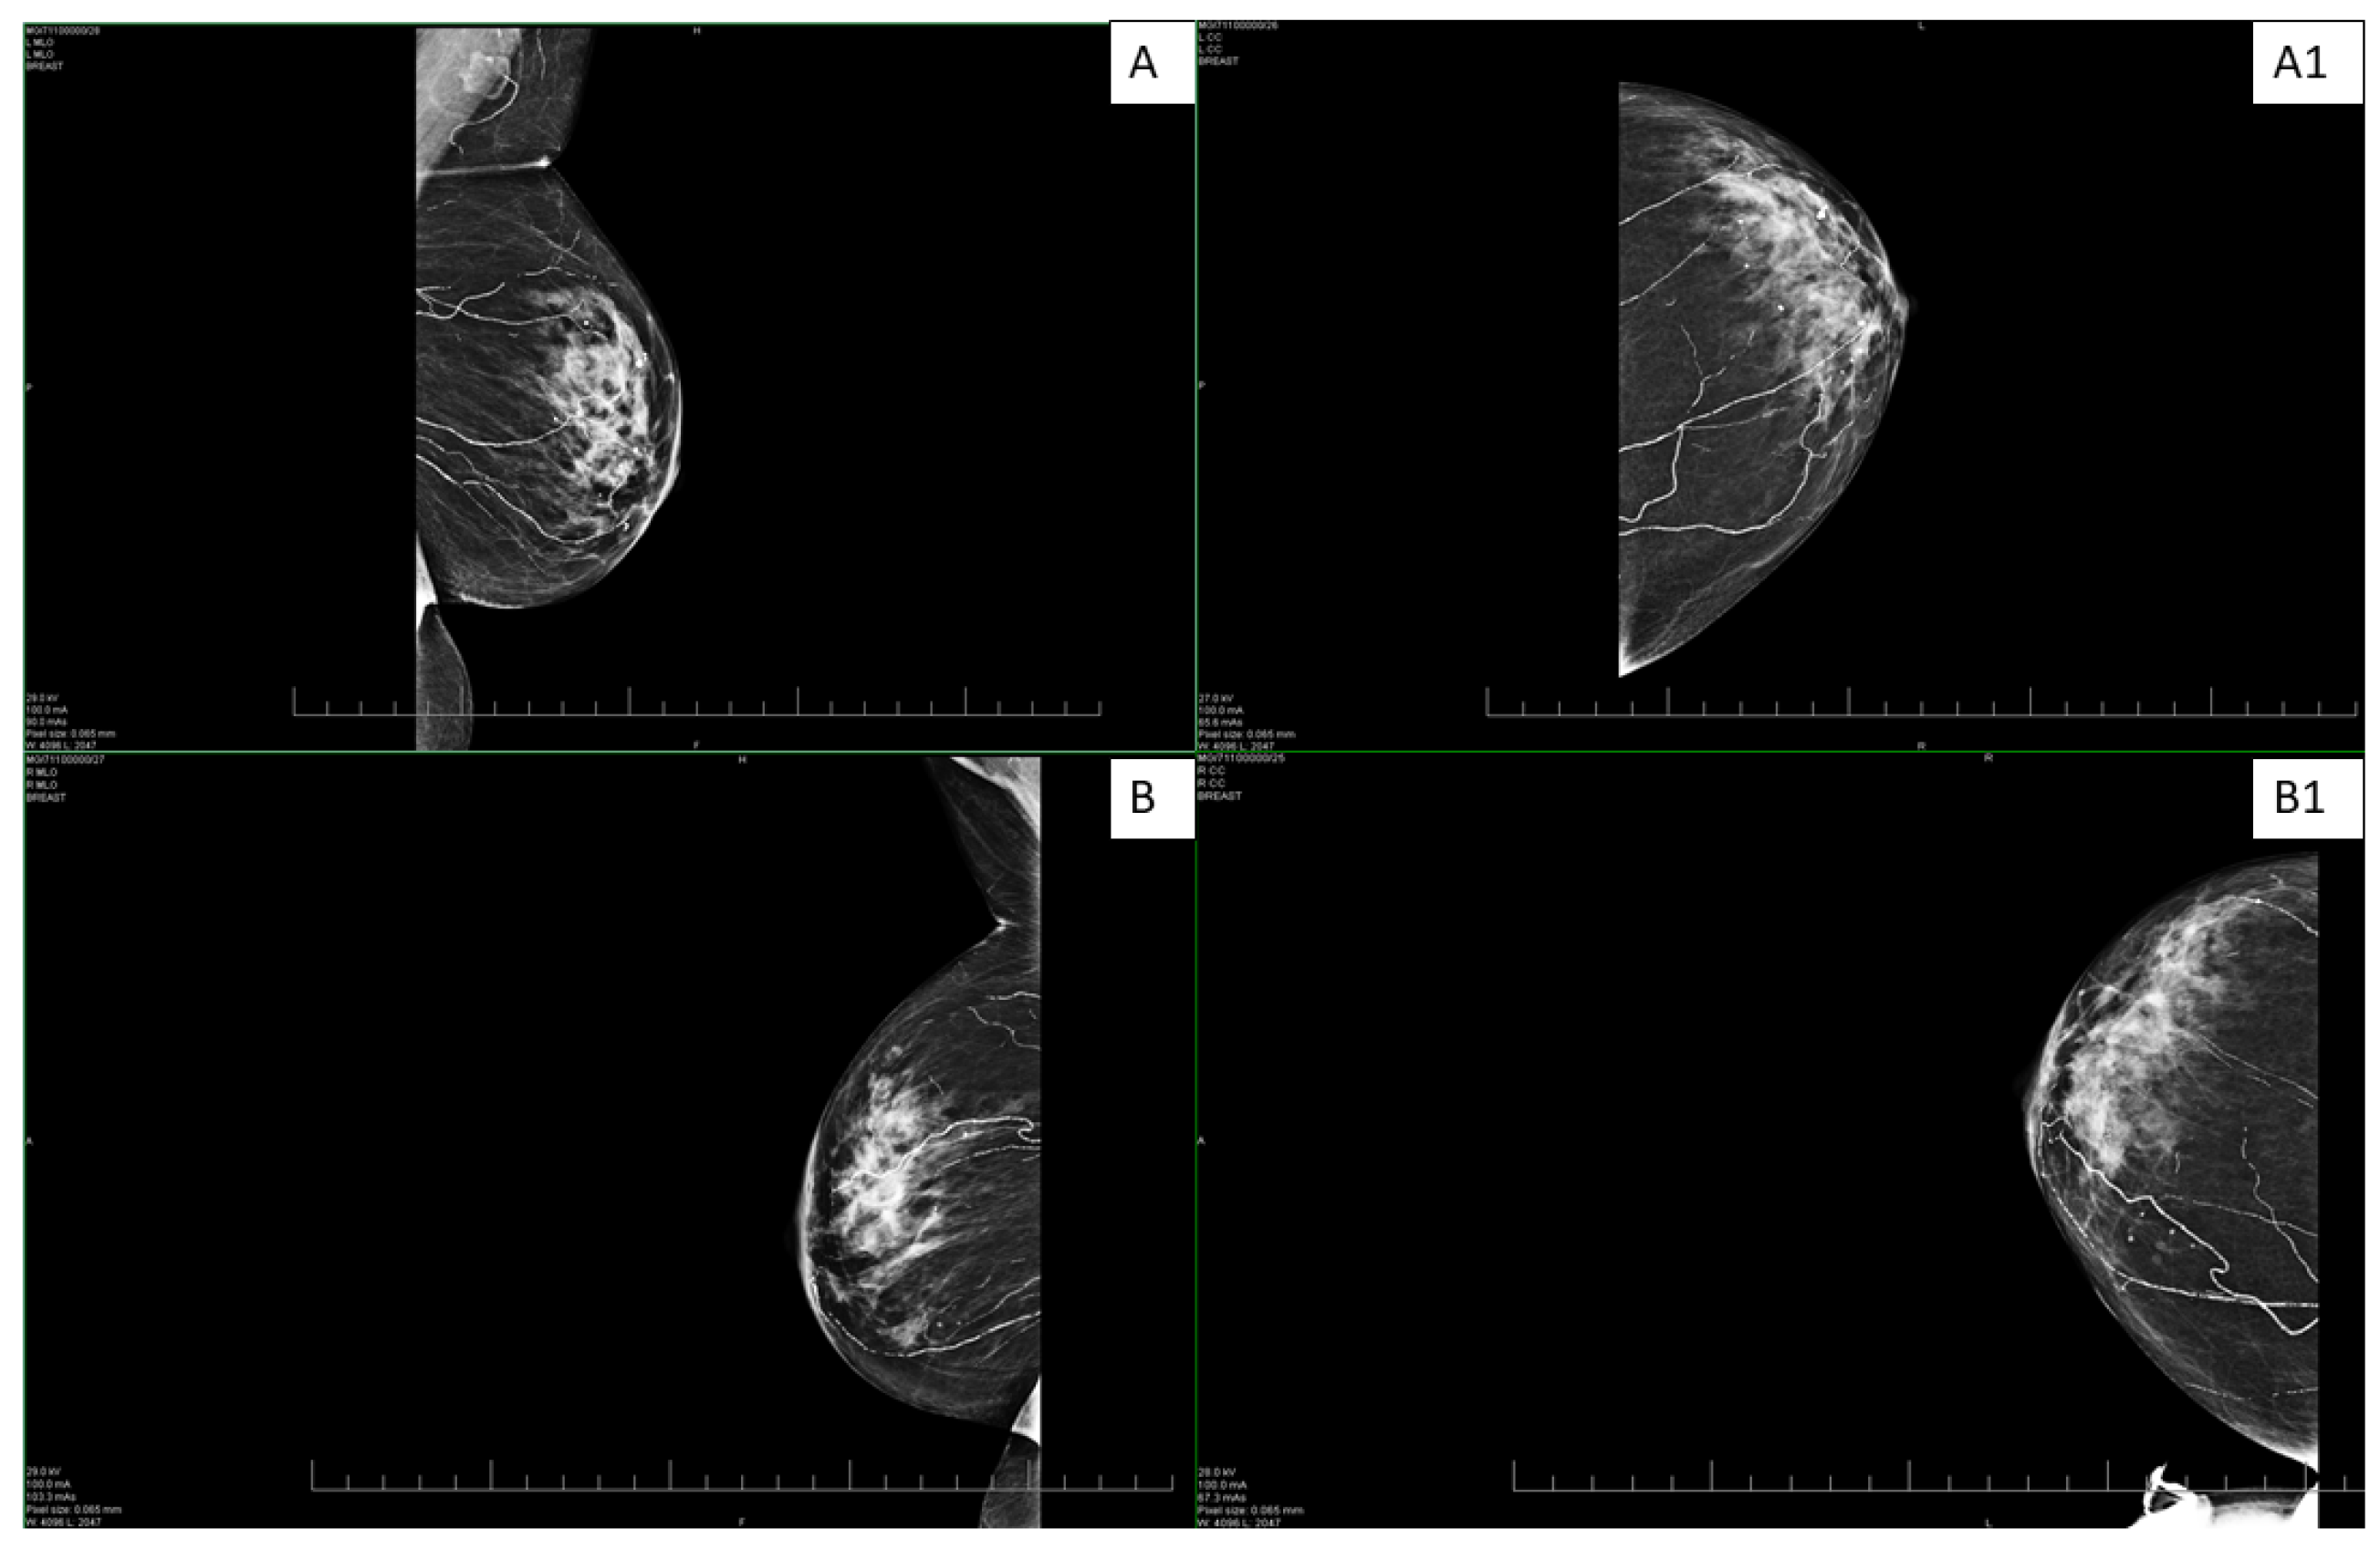

An abdominal ultrasound examination in March 2024 revealed hepatosplenomegaly. A subsequent vascular examination ruled out deep vein thrombosis. Routine CT oncological examination and mammography were negative (Figure 1). The patient underwent a gastroenterological examination, with laboratory parameters showing an increase in GMT to 605.88 U/L and hemoglobin of 86 g/L. The conclusion of the examination described gastritis in the upper gastrointestinal tract and NSAID gastropathy due to analgesic abuse; other parameters and local findings were normal. A biopsy of the lesion in the same month showed that the patient had coagulase-negative Staphylococcus in the wound. The biopsy results also described small vessels with thickened walls and perivascular inflammatory infiltrate. The finding was concluded as nonspecific, not consistent with the picture for vasculitis. On 20 March 2024, the patient was hospitalized at the dermatovenerology clinic for further differential diagnosis of her condition. Laboratory findings again showed an increase in GMT 1319.74 U/L, ALP 334.13 U/L, urea 10 mmol/L, and creatinine 121 μmol/L. The proposed treatment consisted of high doses of methylprednisolone (500 mg intravenously for 3 consecutive days) followed by a reduced dose of 250 mg intravenously and then a gradual transition to tablet form.

Mediocalcinosis is often observed on X-rays around the arteries in the affected area with extension into the surrounding tissue. However, PET/CT scans offer high-resolution images that help define the extent of vascular involvement, which is important for prognosis and treatment planning [13,14]. Mammography, on the other hand, offers high resolution and contrast for the detection of calcifications, which was the case with our patient (Figure 1). Given this, the imaging techniques can contribute to the early identification of calcifications [5,14].

Figure 1. Bilateral digital mammography—standard craniocaudal (A,B) and mediolateral oblique projections (A1,B1) on both sides. The images show scattered microcalcifications and extensive mediocalcinosis on both sides, more pronounced in the left breast.